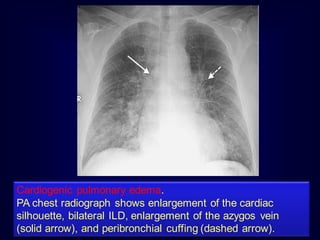

Cardiogenic pulmonary edema.

PA chest radiograph shows enlargement of the cardiac

silhouette, bilateral ILD, enlargement of the azygos vein

(solid arrow), and peribronchial cuffing (dashed arrow).

Lymphangitic carcinomatosis. This 53-year-old man

• 199.

Cardiogenic pulmonary edema. PAchest radiograph shows enlargement of the cardiac silhouette, bilateral ILD, enlargement of the azygos vein (solid arrow), and peribronchial cuffing (dashed arrow).